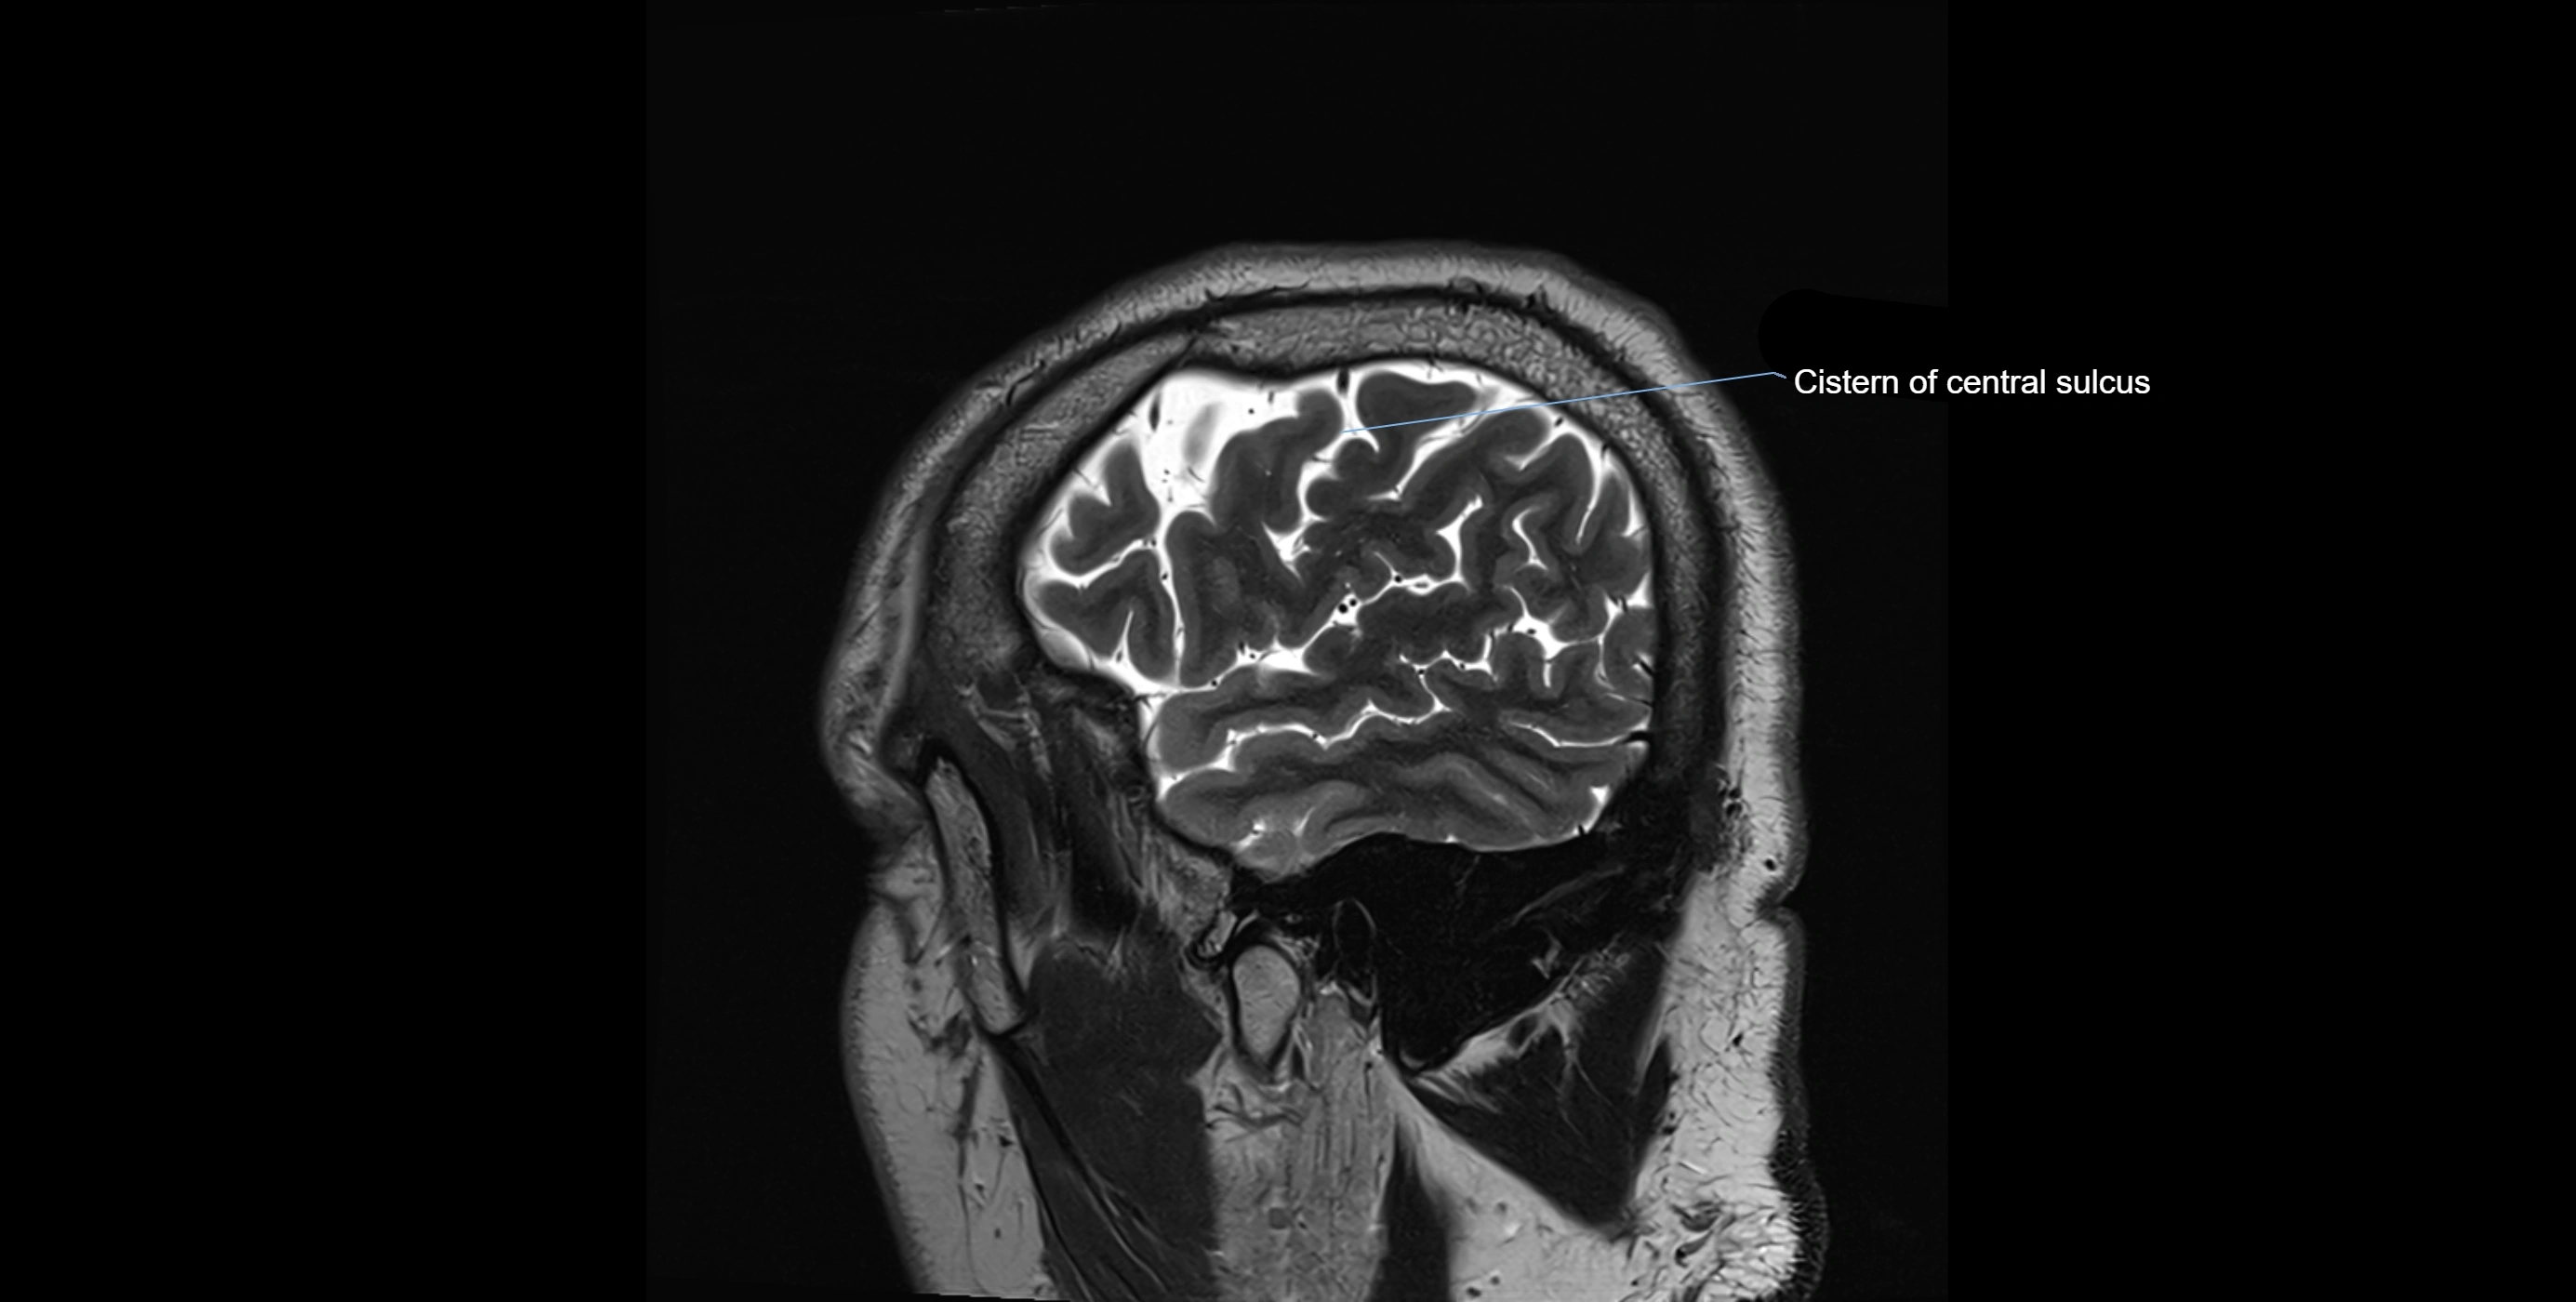

MRI images

image